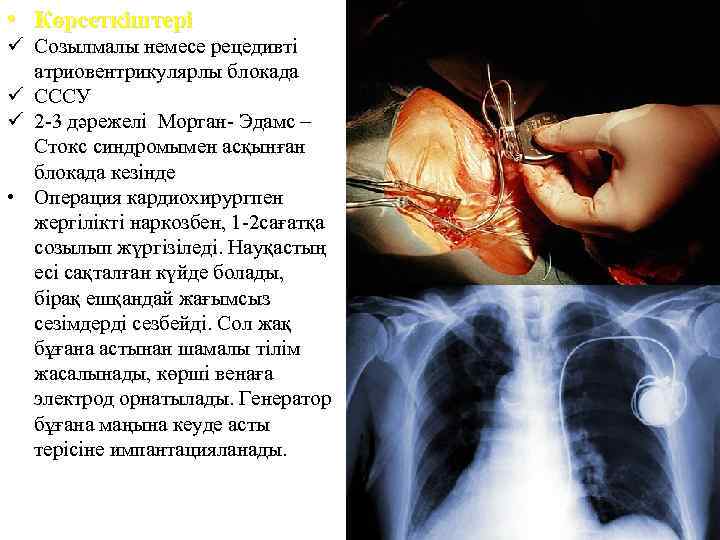

• Көрсеткіштері ü Созылмалы немесе рецедивті атриовентрикулярлы блокада ü СССУ ü 2 -3 дәрежелі Морган- Эдамс – Стокс синдромымен асқынған блокада кезінде • Операция кардиохирургпен жергілікті наркозбен, 1 -2 сағатқа созылып жүргізіледі. Науқастың есі сақталған күйде болады, бірақ ешқандай жағымсыз сезімдерді сезбейді. Сол жақ бұғана астынан шамалы тілім жасалынады, көрші венаға электрод орнатылады. Генератор бұғана маңына кеуде асты терісіне импантацияланады.

• Көрсеткіштері ü Созылмалы немесе рецедивті атриовентрикулярлы блокада ü СССУ ü 2 -3 дәрежелі Морган- Эдамс – Стокс синдромымен асқынған блокада кезінде • Операция кардиохирургпен жергілікті наркозбен, 1 -2 сағатқа созылып жүргізіледі. Науқастың есі сақталған күйде болады, бірақ ешқандай жағымсыз сезімдерді сезбейді. Сол жақ бұғана астынан шамалы тілім жасалынады, көрші венаға электрод орнатылады. Генератор бұғана маңына кеуде асты терісіне импантацияланады.